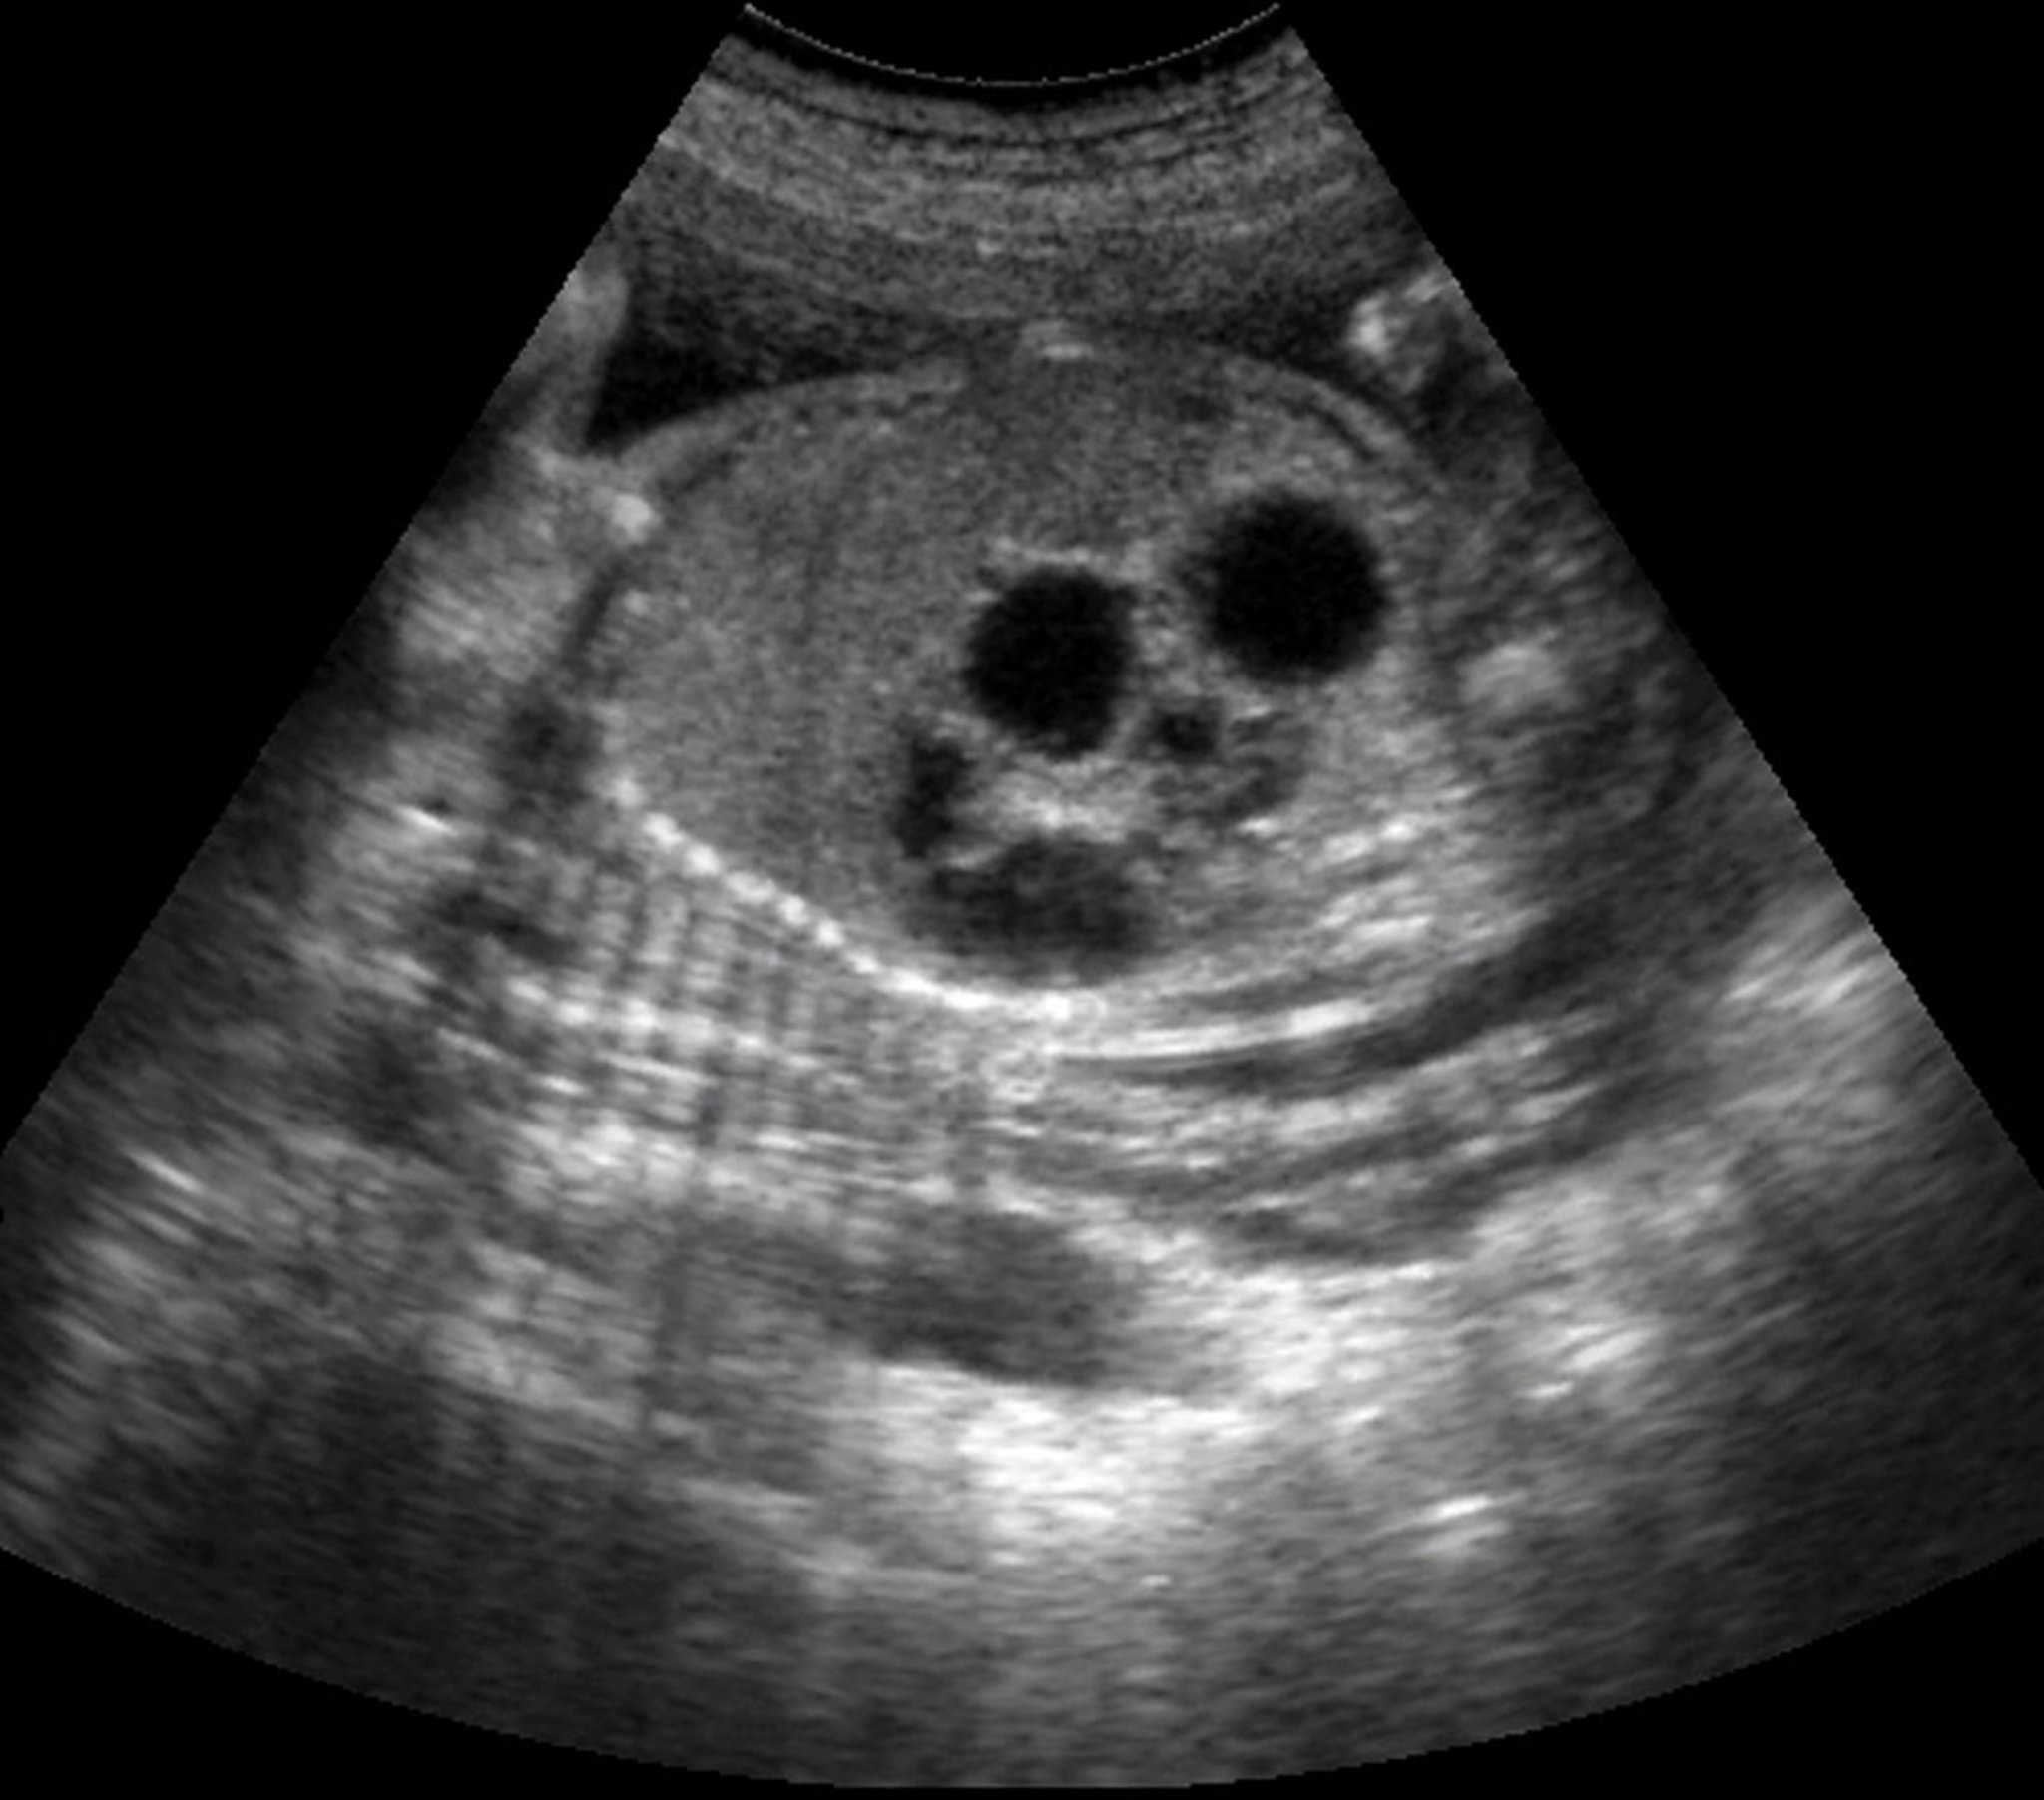

El diagnóstico de atresia duodenal se sospecha antes del nacimiento si hay polihidramnios y/o dilatación del estómago. La ecografía prenatal puede detectar un signo de doble burbuja (una gran burbuja gástrica y una burbuja duodenal proximal más pequeña) en hasta el 80% de los casos (2).

Esta imagen de ecografía muestra el signo de doble burbuja en un feto con atresia duodenal.

Esta radiografía muestra el típico signo de doble burbuja observado en la obstrucción duodenal completa. La burbuja más pequeña representa el duodeno proximal dilatado (flecha blanca); la burbuja más grande representa el estómago (flecha negra). Este signo puede observarse en la atresia duodenal, la membrana duodenal, el páncreas anular y la vena porta preduodenal. En raras ocasiones, también se puede ver con obstrucción duodenal completa como resultado de la presencia de bandas de Ladd en un paciente con malrotación.